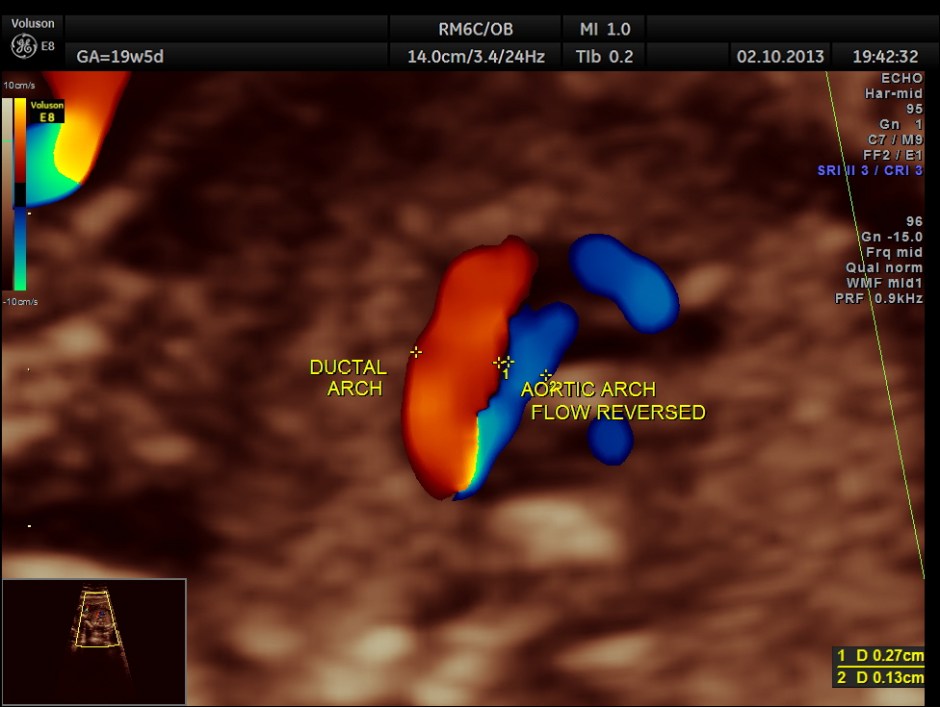

Aortic arch is progressively narrowed with the isthmus appearing very narrow. A flow reversal is also seen .